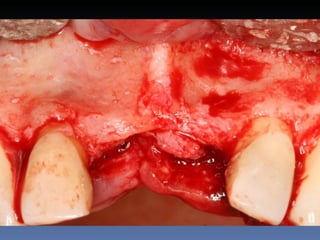

BOX 3

Kátia Maria Cavicchia

Idade – 43 anos

Sexo – Feminino

Raça – Caucasiana

ASA – II

Data- 29-04-2012

Diagnóstico: Desdentado parcial

bilateral posterior da mandíbula.

Plano de tratamento: Reabilitação bilateral posterior

mandibular com instalação de 6 implantes endo-

ósseos, para reabilitação protética fixa.

Zona 4.4, 4.5, 4.6   Zona 3.5, 3.6, 3.7